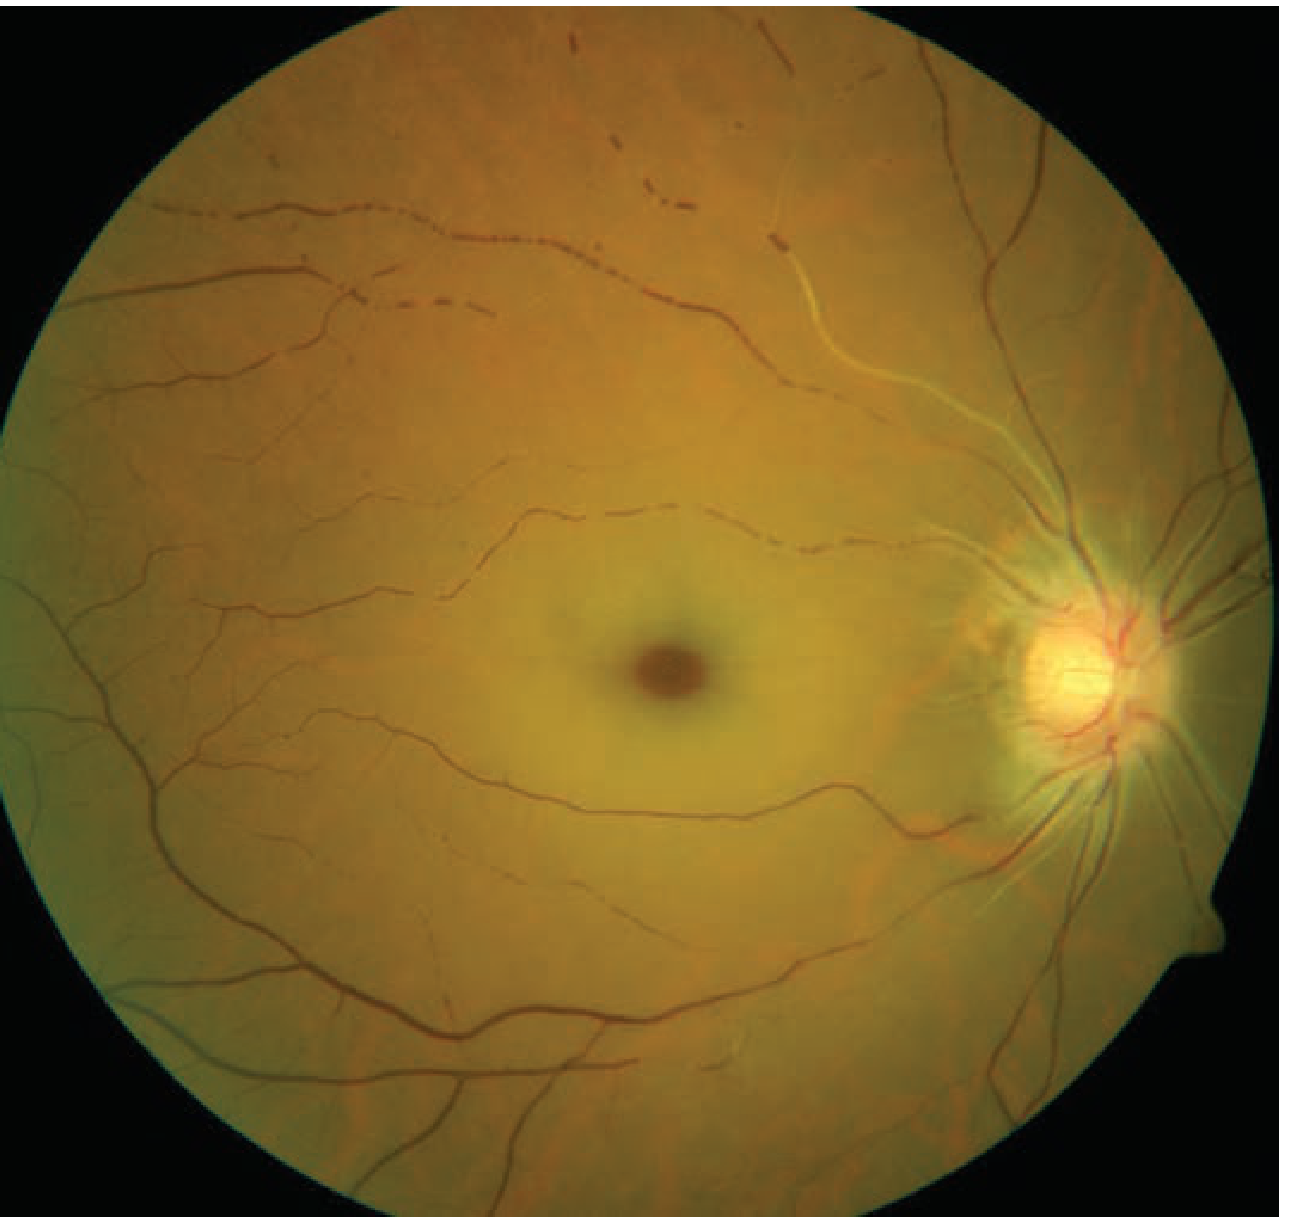

Fundus Appearance

Classic CRAO (Tintinalli's Emergency Medicine):

CRAO fundus showing cherry-red spot and retinal pallor with Hollenhorst plaques

Diffuse retinal pallor with macular cherry-red spot. Note the attenuated arterioles.